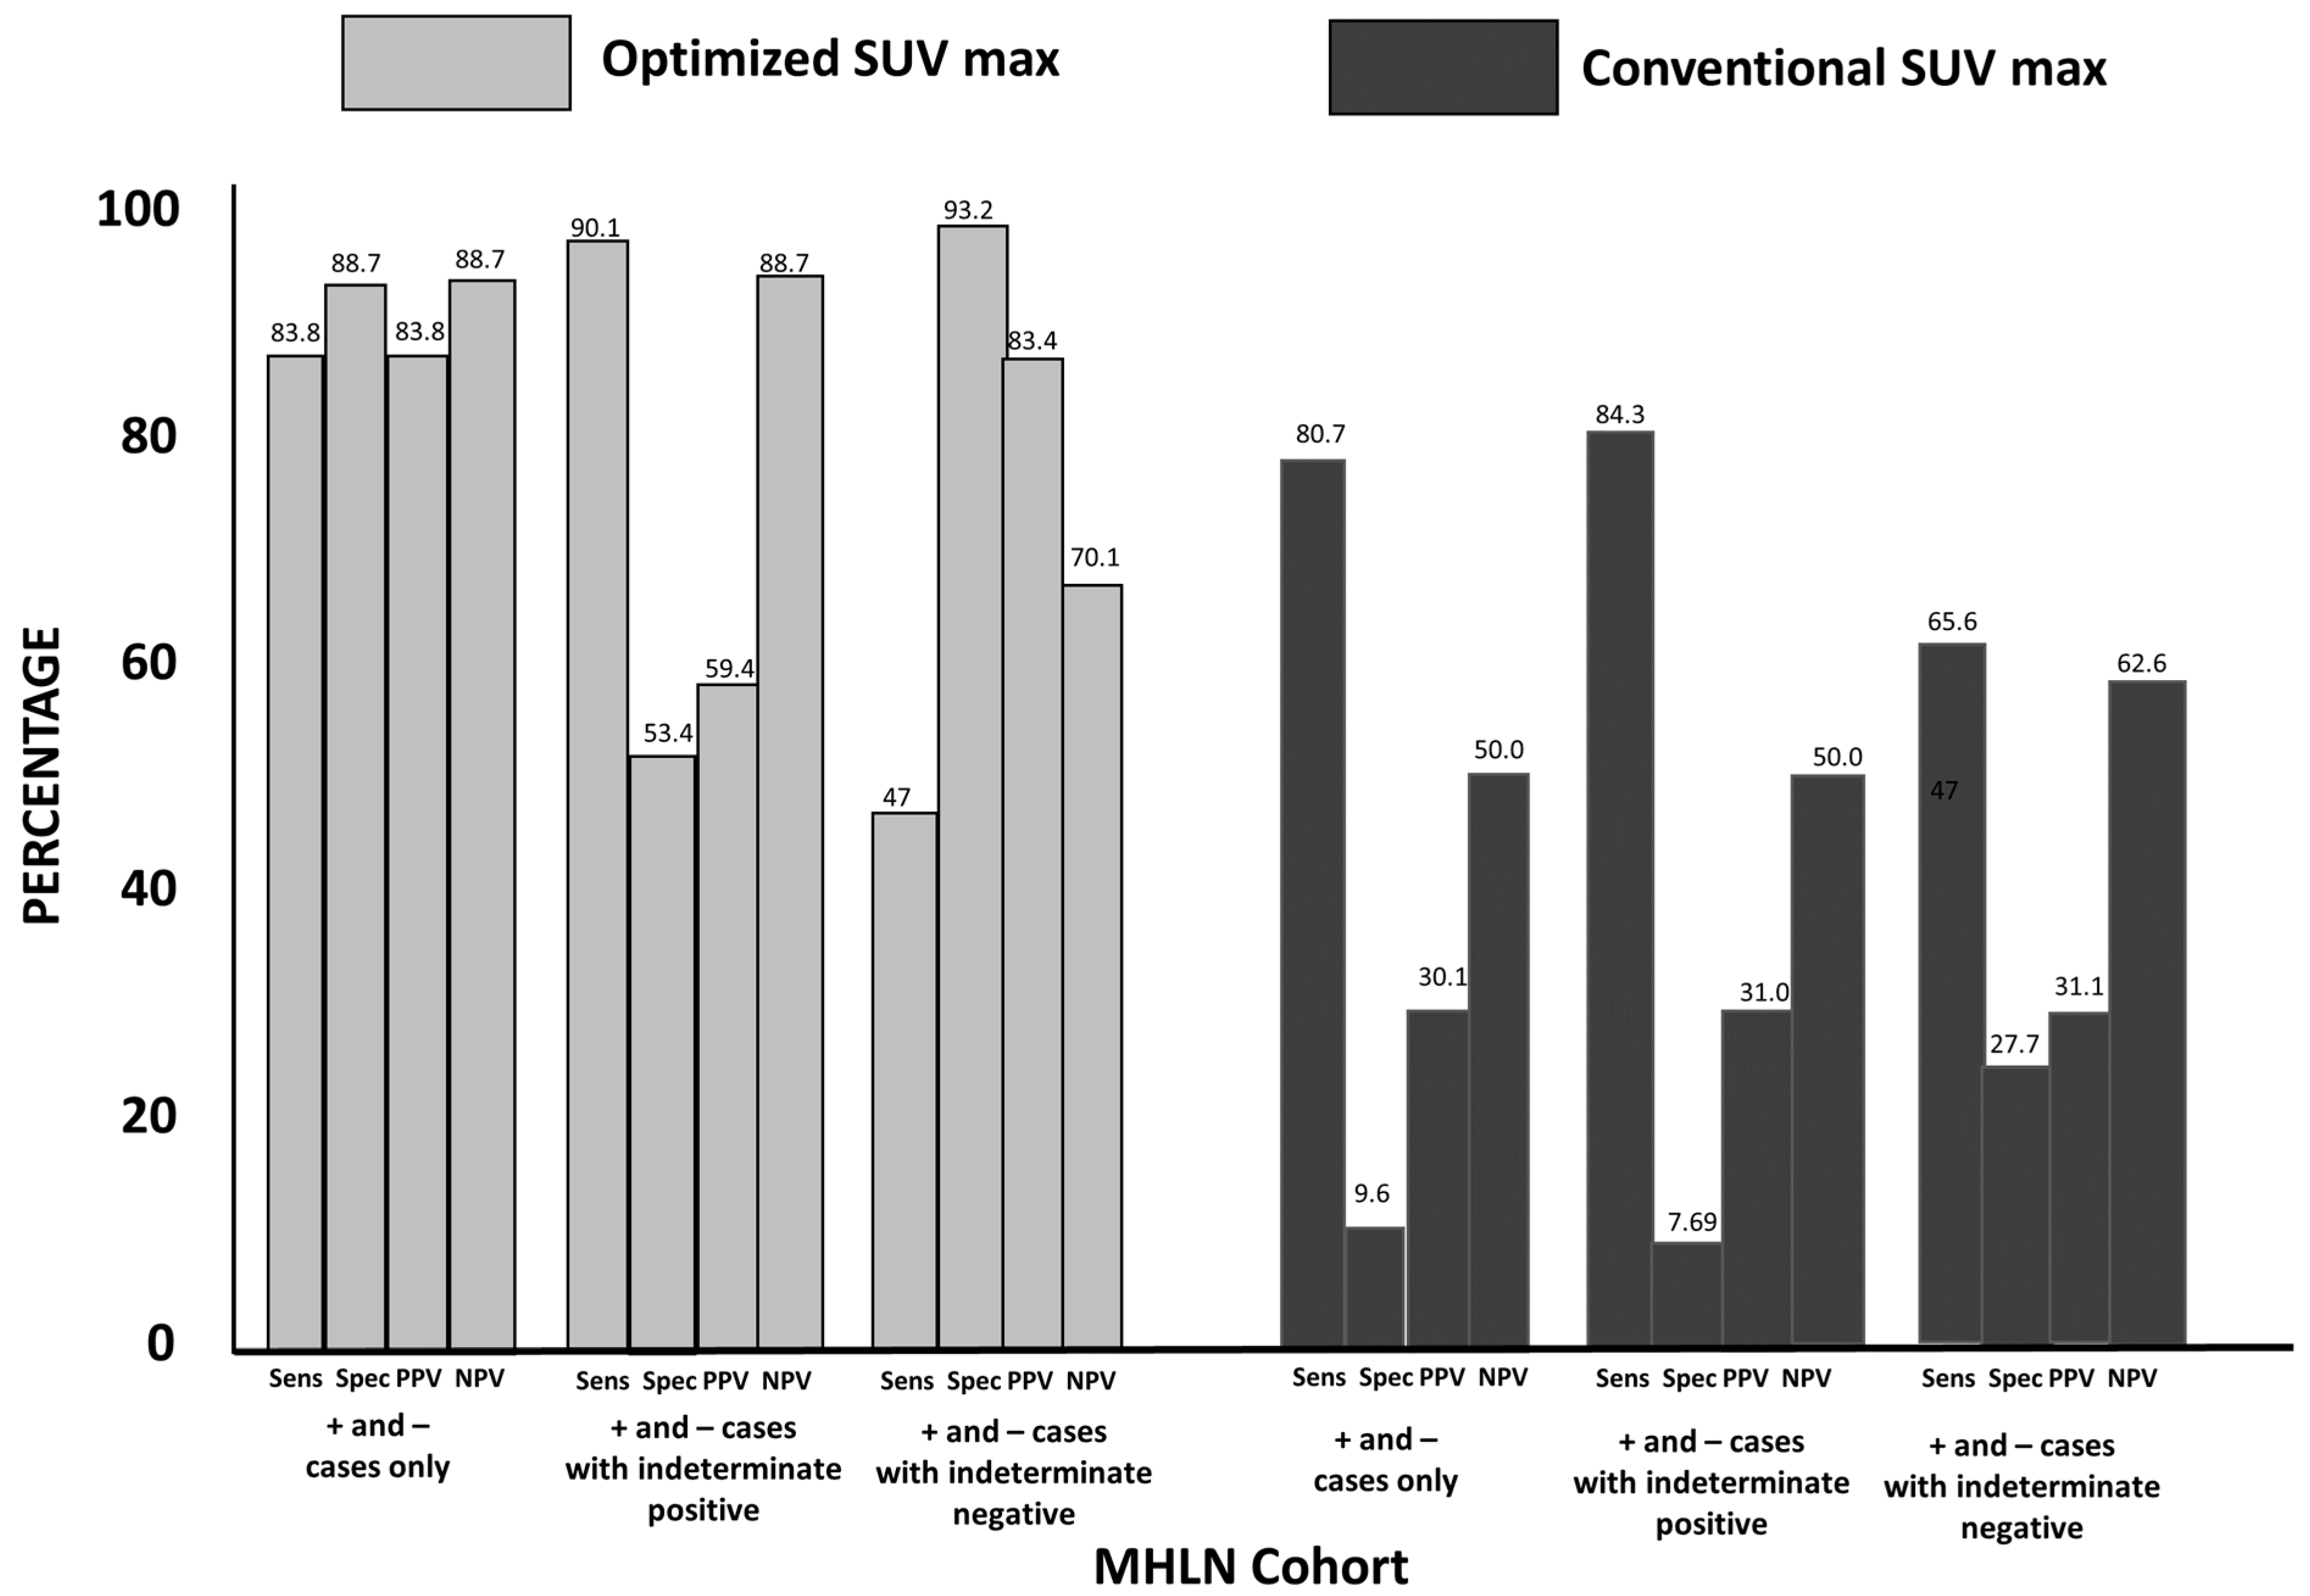

3.2. Group 1: MHLN Lung Cancer Cohort

3.3. Group 2: ETLN Cohort